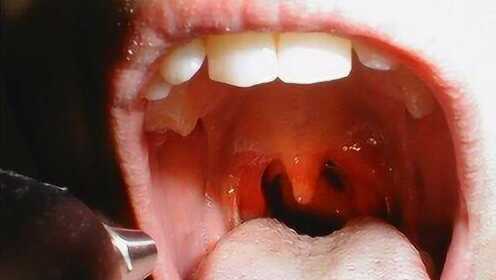

慢性咽炎是一種常見的喉部疾病,主要表現(xiàn)為咽部不適、干燥、瘙癢、疼痛等癥狀,由于長期受到刺激或感染,咽部黏膜出現(xiàn)慢性炎癥表現(xiàn),慢性咽炎雖然不是嚴(yán)重疾病,但癥狀反復(fù)發(fā)作,嚴(yán)重影響患者的生活質(zhì)量。